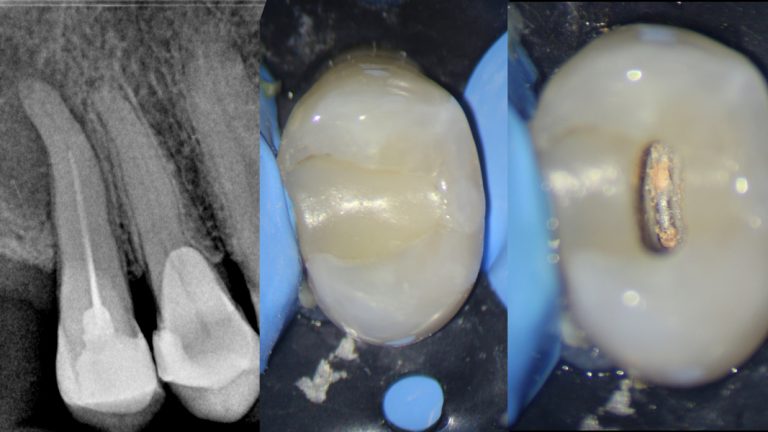

El doctor Roberto Estévez nos muestra las ventajas de trabajar con las limas BlueShaper en un primer premolar…